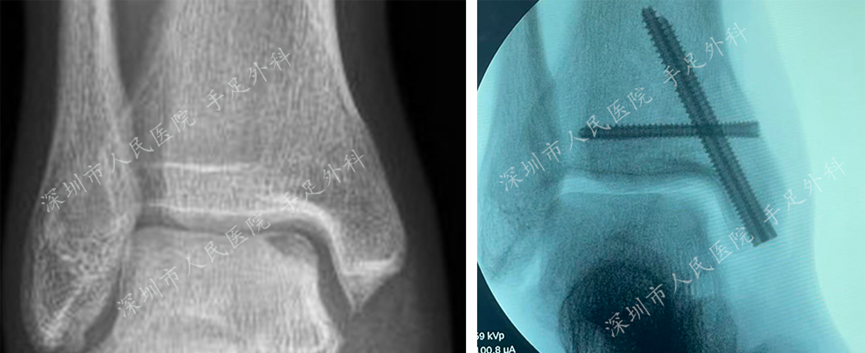

图11:X光片示手术前(左)和手术后(右)对比